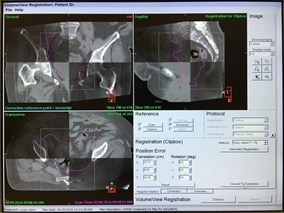

In occasione della prima seduta di RTE vengono simulati i vari campi di trattamento, confrontati con DRRs (digitally reconstructed radiographs ) derivate dall' elaborazione delle immagini volumetriche di riferimento oppure veiene eseguito il match delle immagininI della CBCT con le immagini Tc di riferimento.

CBCT